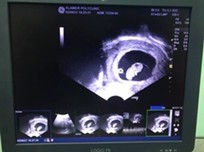

ซาวด์ตอน6+6ค่ะ แต่เครื่องบอก6+4 เห็นหัวใจแล้วค่ะ คุณหมอชี้ให้ดู คุณหมอบอกที่กระพริบๆอยู่อันนั้นคือหัวใจ

นับตามประจำเดือน 7 วีค แต่ในใบซาวน์ 6วีค 4วันค่ะ เจอตัวน้อยพร้อมหัวใจเต้น ซาวน์ผ่านหน้าท้องค่ะ